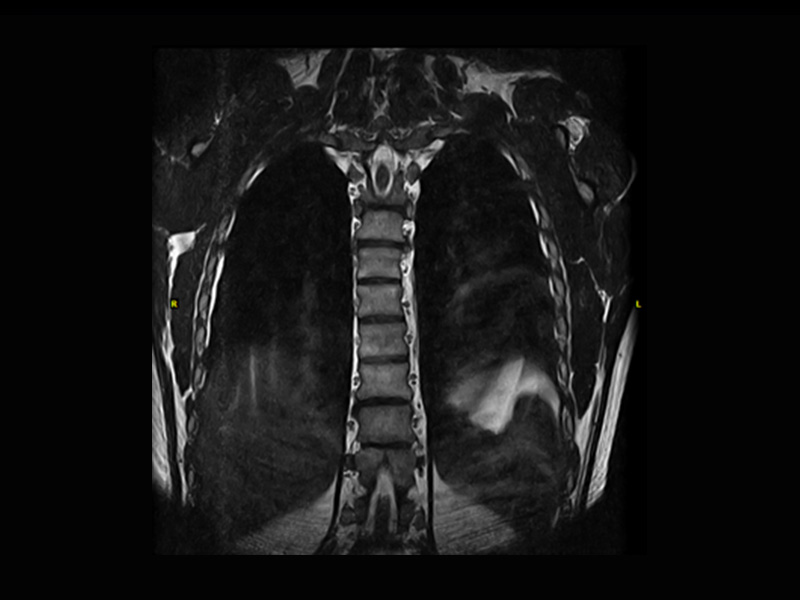

Klinické snímky